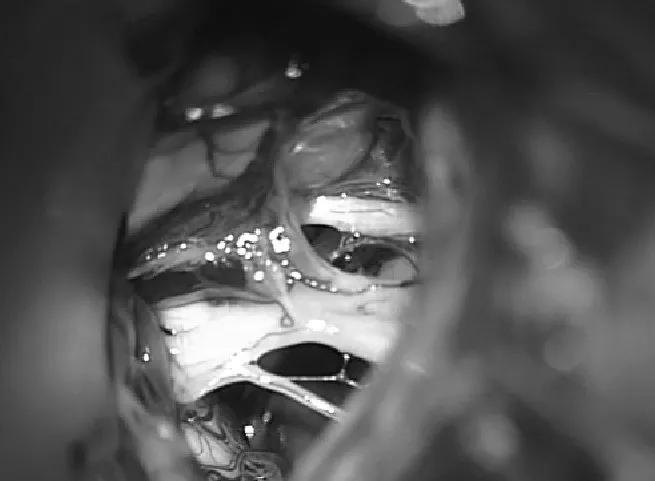

抽吸脑脊液后,仔细地从周围血管和神经结构上解剖囊肿壁,以获得全切(图2)。